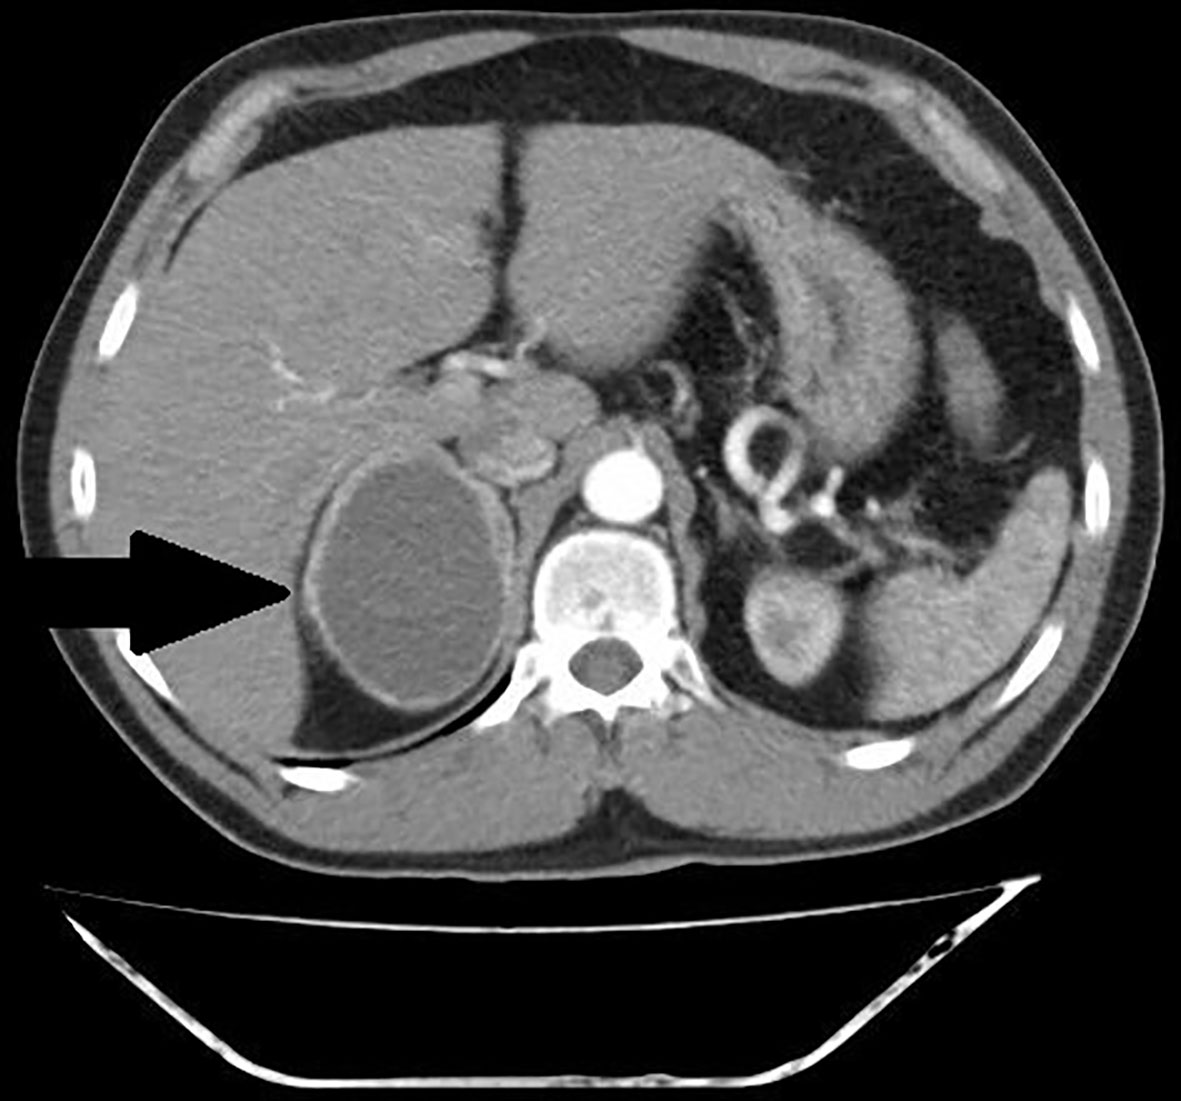

FIGURE 3

www.frontiersin.org

Figure 3 Patient number 4: CT of the abdomen, arterial phase, axial image- thick – walled hemorrhagic cyst of right adrenal gland with strong capsule-contrast enhancement (thick arrow).